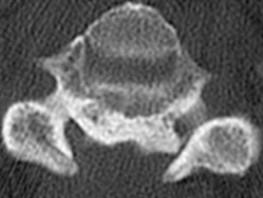

问题 女,58岁,颈部疼痛,活动受限,请结合图像,选出最可能的诊断 ( )

选项 A、椎间盘突出 B、局限性骨化性肌炎 C、颈椎结核 D、椎缘骨 E、颈椎退行性变

答案 E